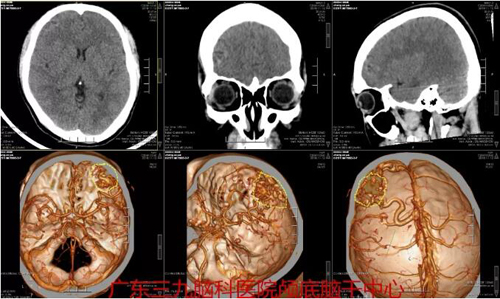

图2:术前CTA检查示:1.右侧额叶动静脉畸形,主要由右侧大脑中动脉上干异常分支供血,相应引流静脉汇入上矢状窦。